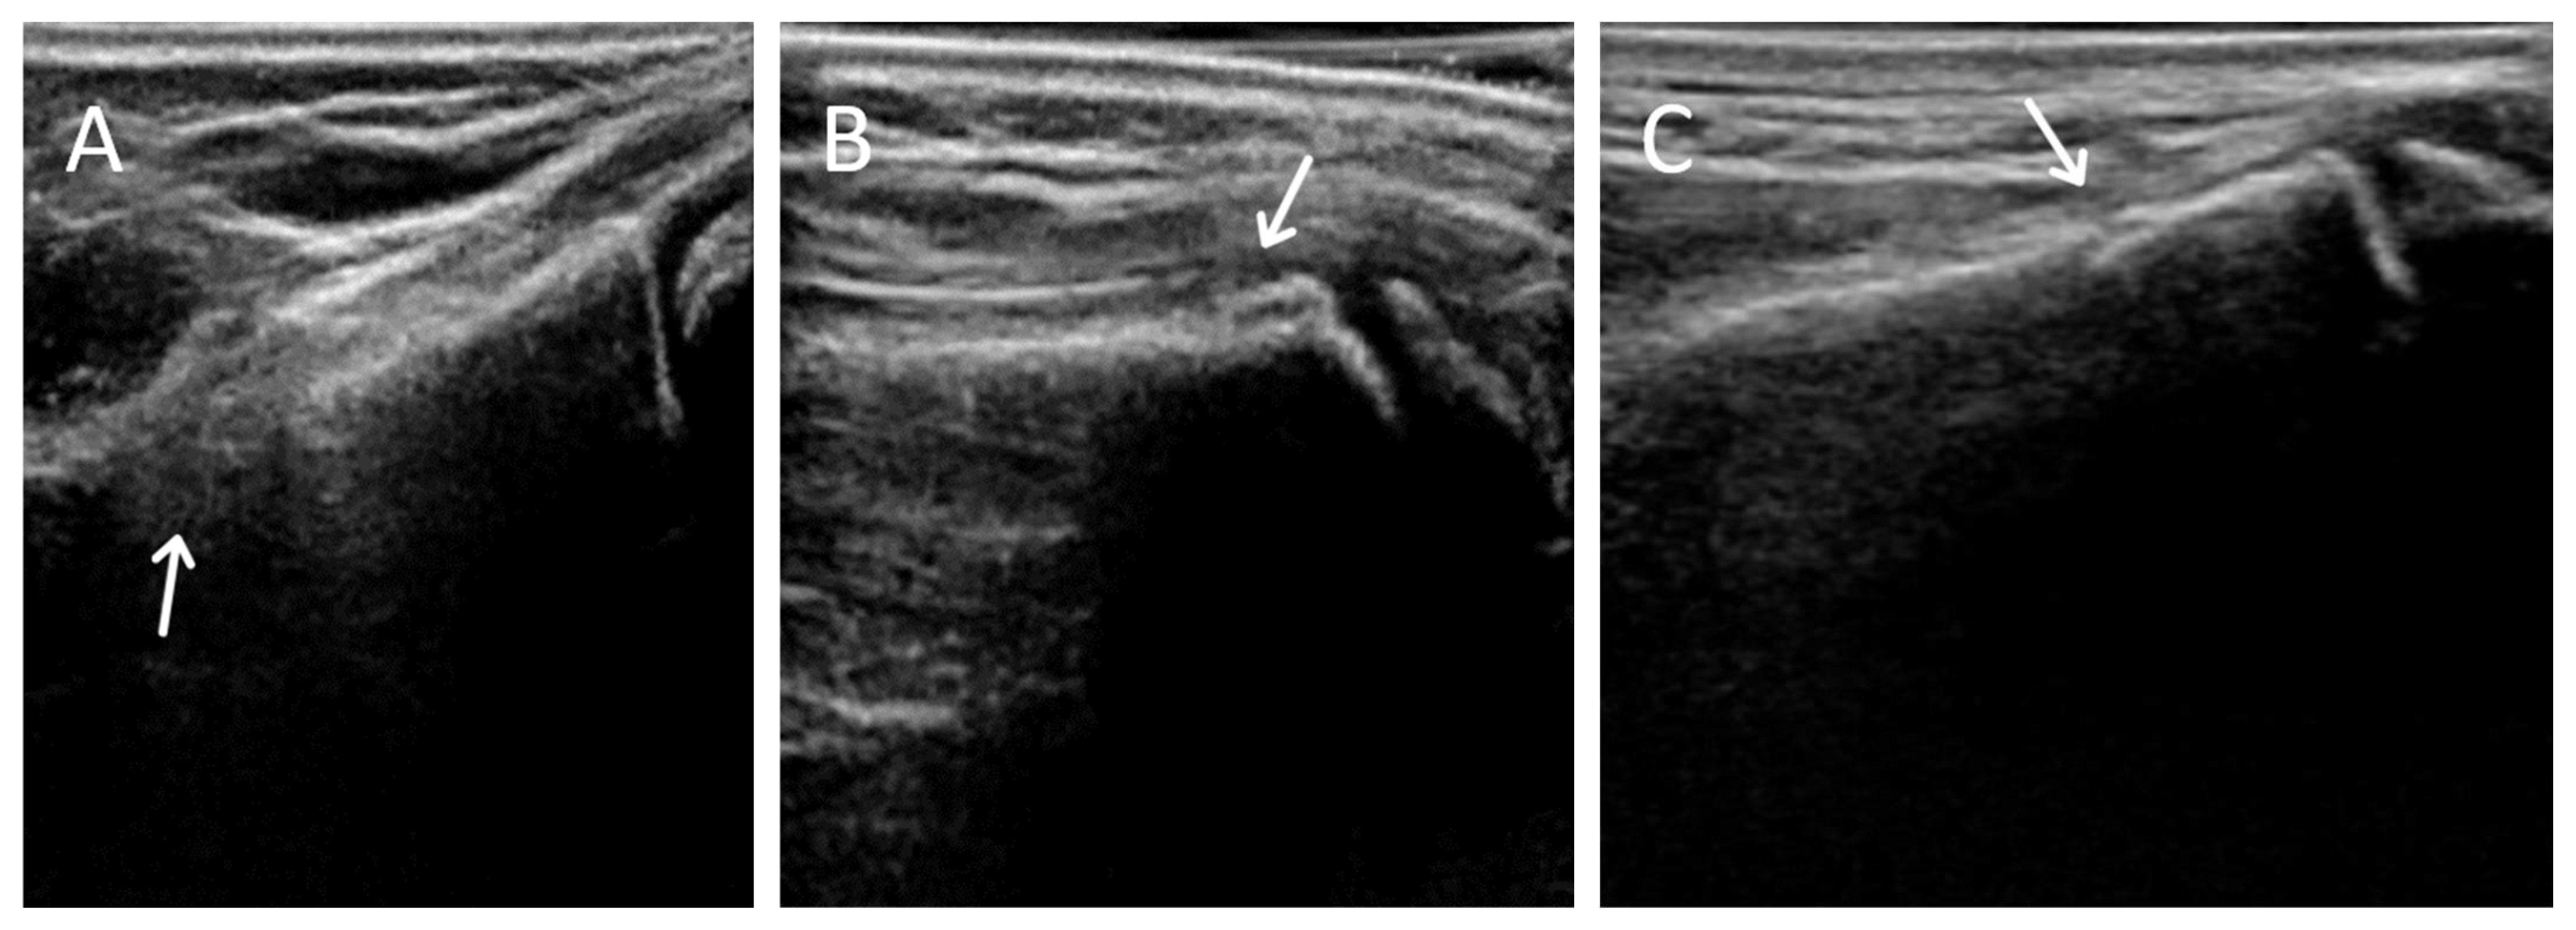

Reviewing the discordant cases, there were several individual reader false positives, with the false-positive rate reduced by using the combined reading values, further suggesting the need for more training. Another reason for false positives was US artifacts, including double or interrupted cortical margins, likely caused by motion artifact and side-lobe artifact. The 3DUS obtained hundreds of images per sweep, and some of these images included artifacts that might not be identified as frequently on 2DUS. Adding 5 min of user training specifically demonstrating examples of these artifacts could help users avoid misinterpretation. Users who identify these artifacts at the time of scanning would be encouraged to perform repeat scans, subject to time constraints in the clinical department.

Figure 3. Examples of 3DUS scanning artifacts. (A) Edge effects, (B) double cortex from motion, (C) overlapping cortex.